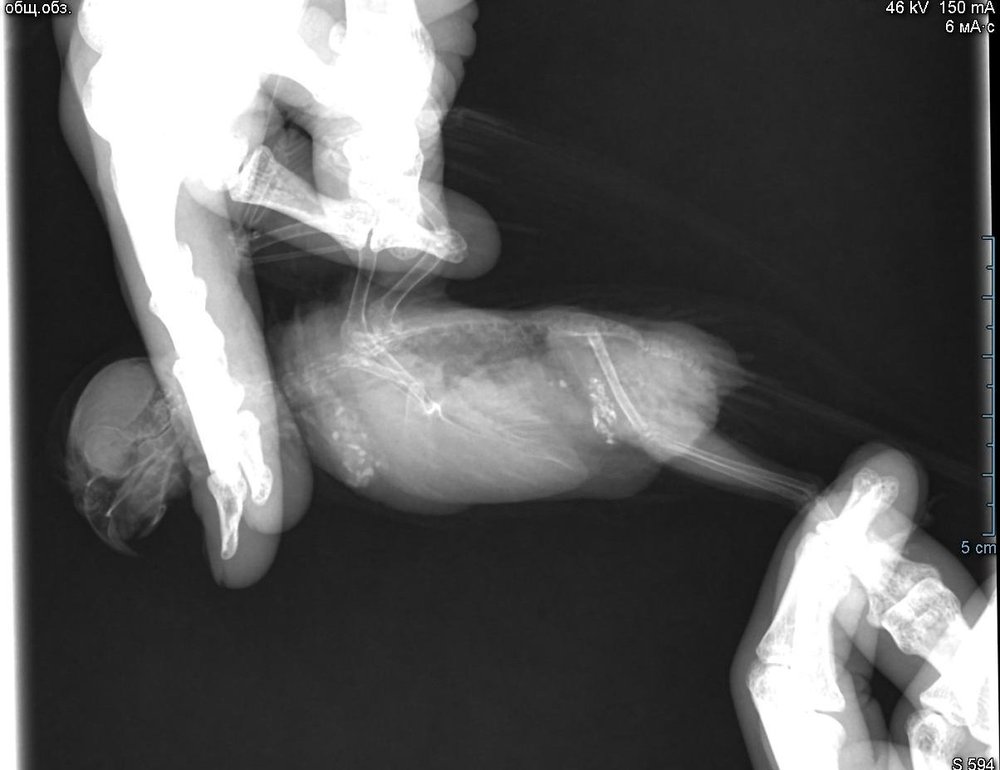

Во вторник отвозила птицу на рентген. Врач сказала, что очень сильно увеличена печень и другие органы. Также сдавлены воздухоносные мешки (из-за увеличенных внутренних органов). Отсюда - одышка. Также врач нашла перелом (старый?) ключицы. Попугая было очень сложно удерживать, поэтому снимки получились, возможно, недостаточно информативными - но какие уж получились((

@Zosia здравствуйте! Посмотрите, пожалуйста, снимки - видите ли вы на них отклонения, опухоли? Есть ли какие-то патологии? И одобряете ли вы назначенное лечение в нашей ситуации? Спасибо!

2.jpg

4.jpg

Печень видится мне увеличенной, но нужно чтобы @Zosia достоверно прочла снимки.

ответ: я увидела на снимках запущенную пневмонию, увеличенные семенники (и возможно опухоль на них), увидела в помете много палочек. Отсюда - назначение.

6.Тень семенников действительноу величена. Но снимок вами показан дурного качества. И бОльшего я сказать не могу.